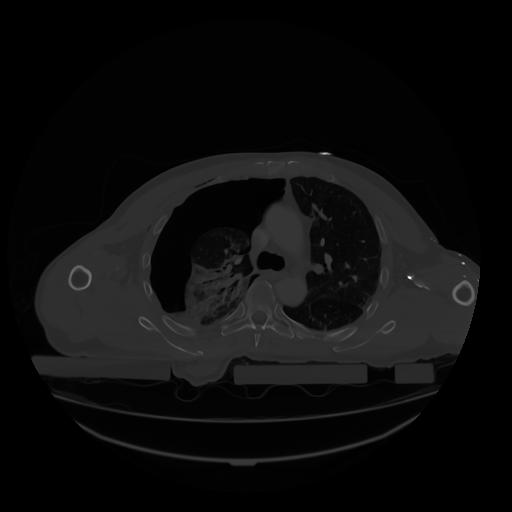

28 CUERPO,CE,Vol,2.0,CUERPO,,